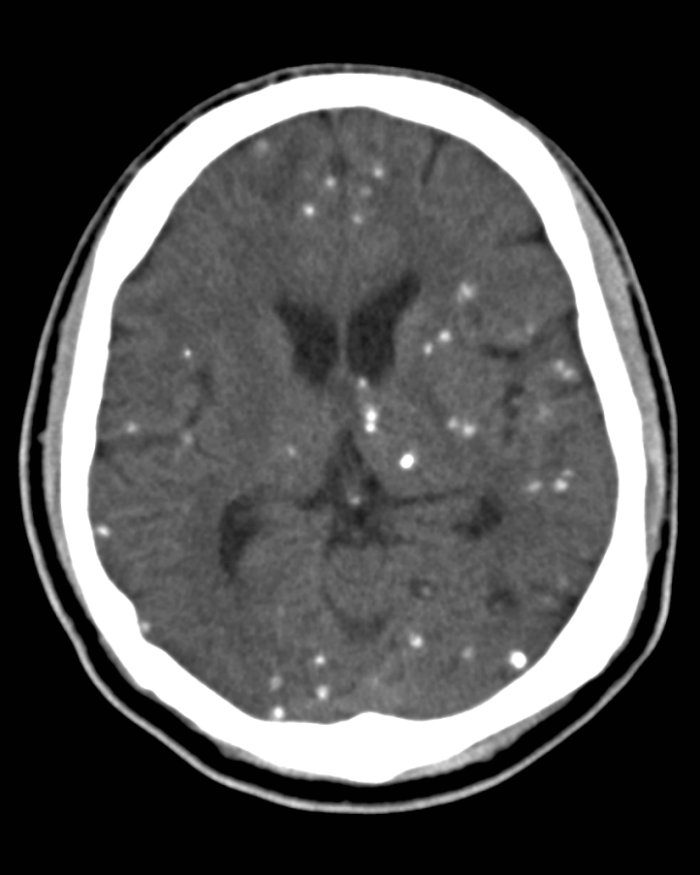

Processo evolutivo natural que dura de 2 a 5 anos e que culmina na degeneração do cisticerco, o processo é dividido em 4 etapas (vesicular, coloidal, granular e calcificado)

Na cisticercose, as formas larvais provocam uma reação inflamatória que, por um período de tempo, sofre calcificação. Os cistos podem estar presentes no cérebro, olhos, músculo esquelético e tecidos subcutâneos.

- Nodular, nódulo sólido rodeado por tecido conjuntivo denso formando um granuloma.